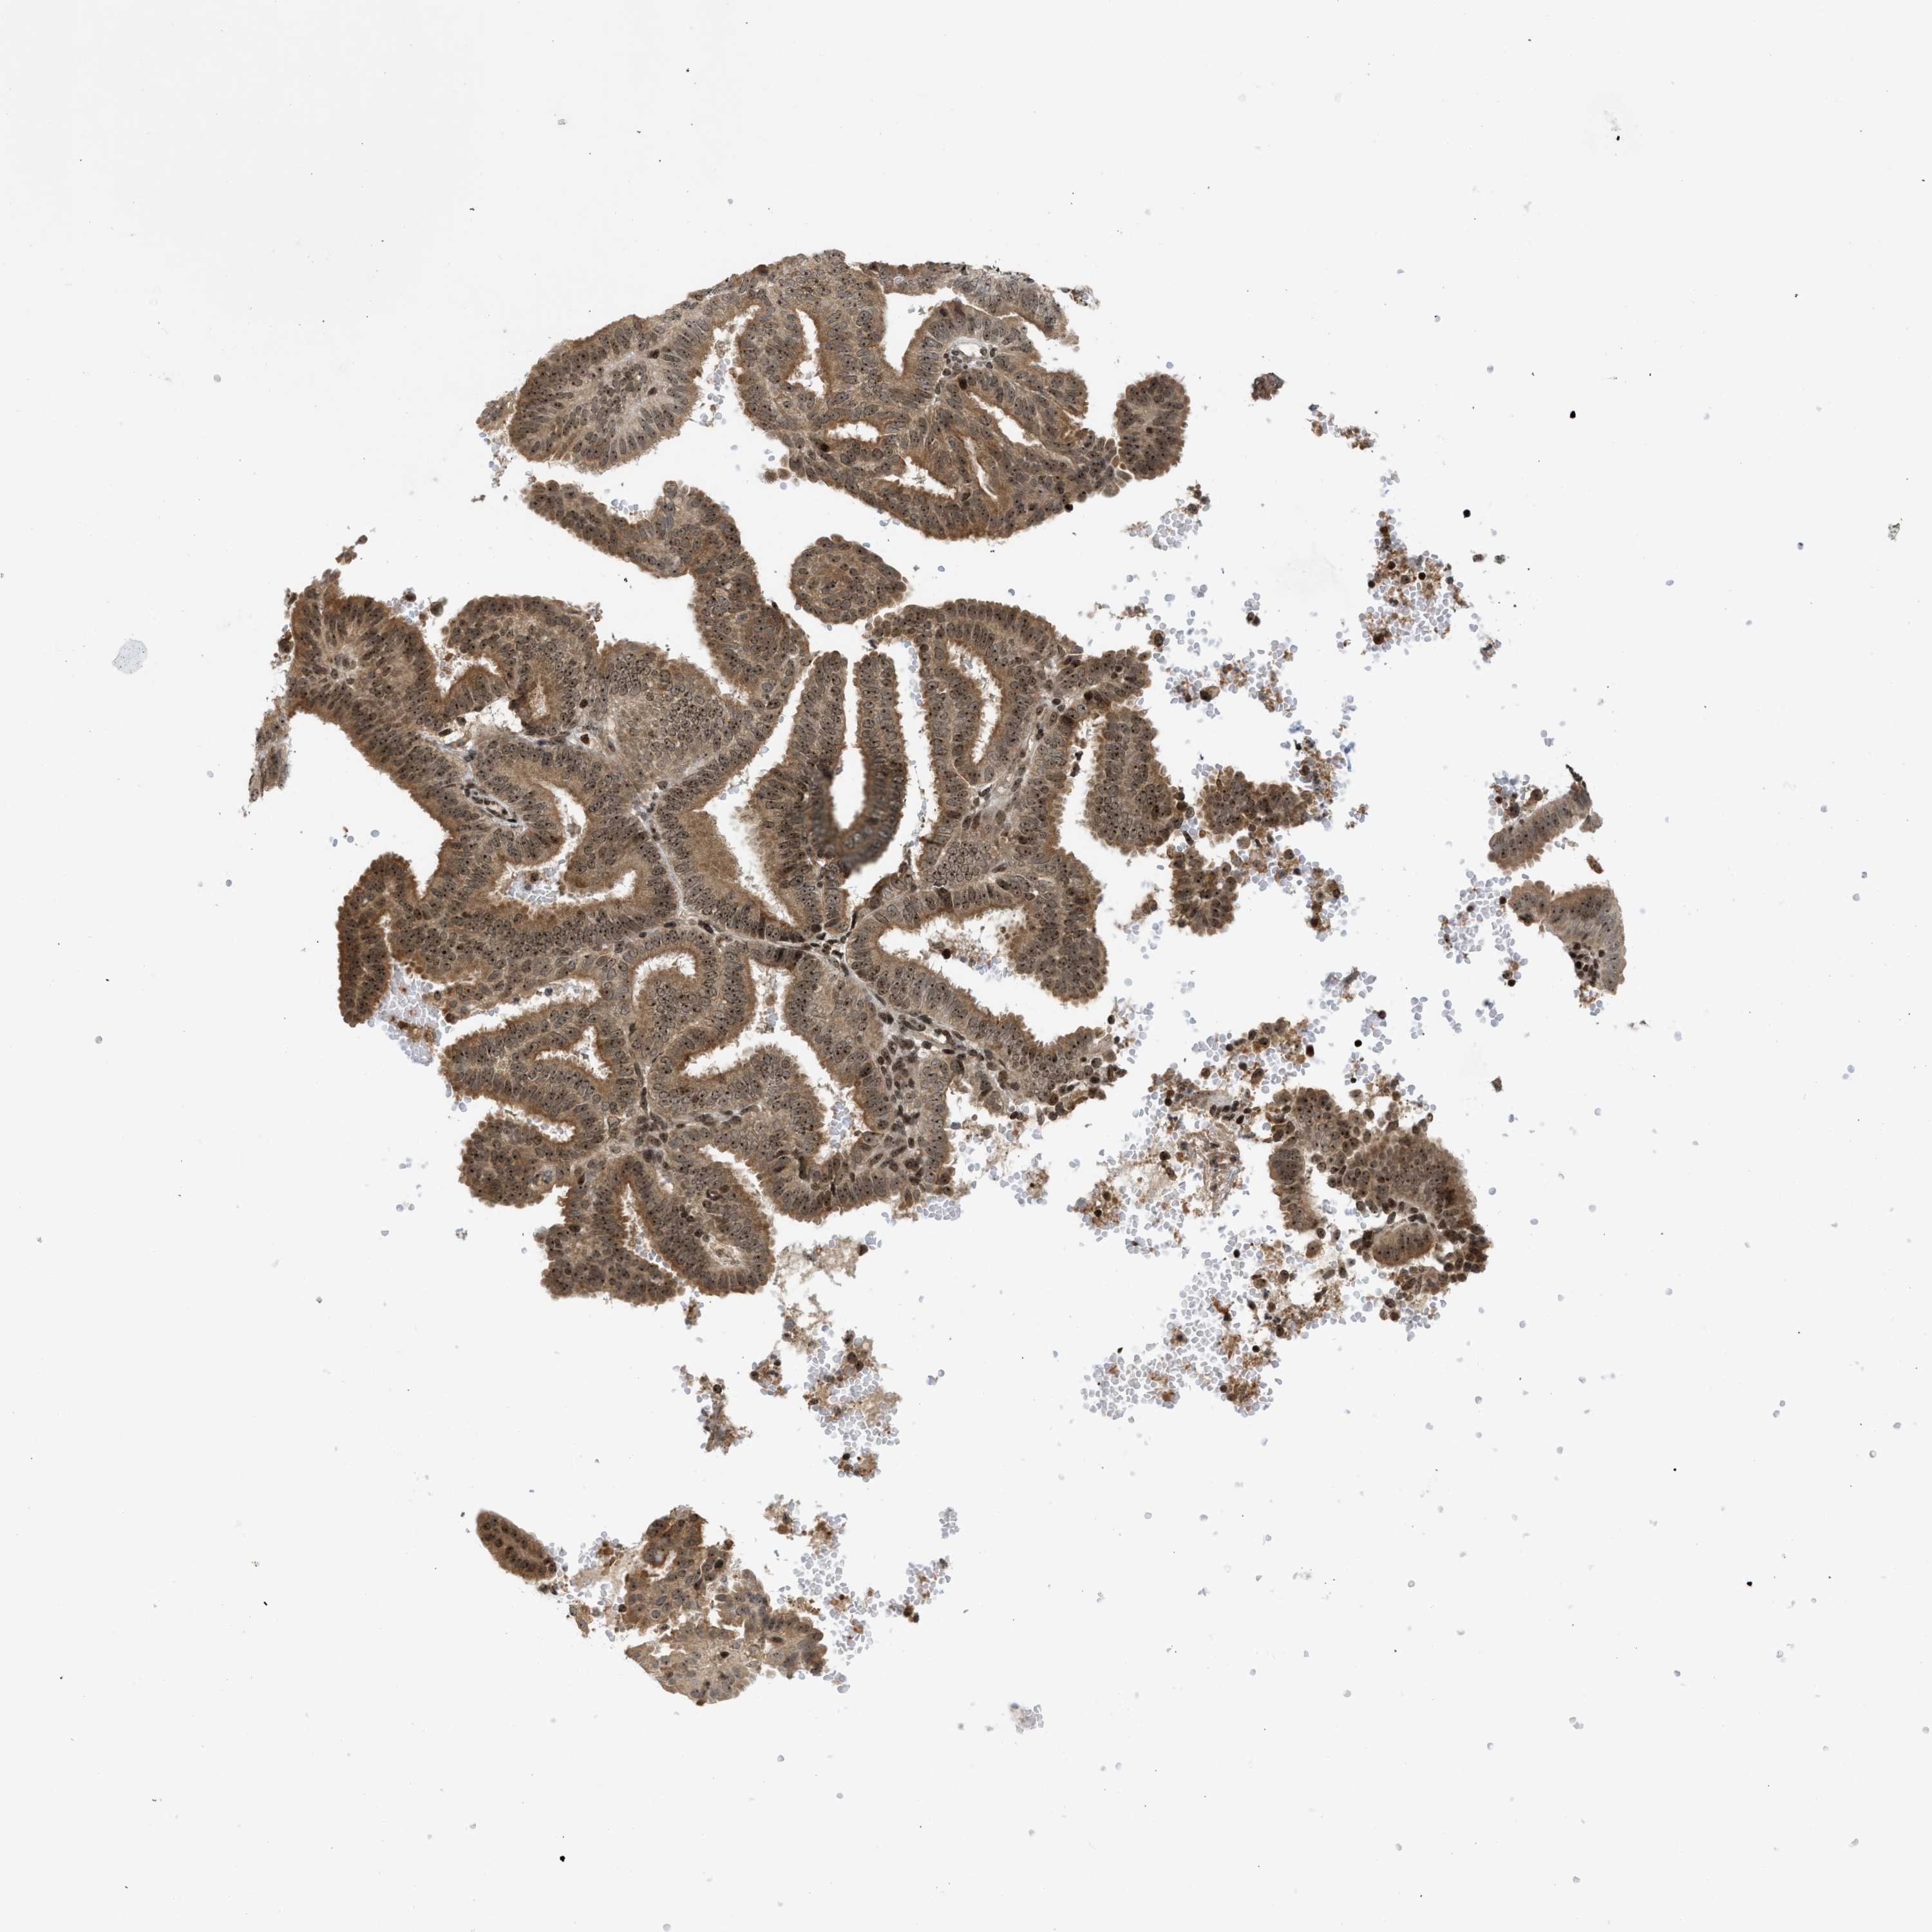

ENDOMETRIAL CANCER - Protein expressioni

A mouse-over function shows sample information and annotation data. Click on an image to view it in a full screen mode. Samples can be filtered based on level of antibody staining by selecting one or several of the following categories: high, medium, low and not detected. The assay and annotation is described here.

Note that samples used for immunohistochemistry by the Human Protein Atlas do not correspond to samples in the TCGA dataset.

Antibody stainingi

Antibody staining in the annotated cell types in the current human tissue is reported as not detected, low, medium, or high, based on conventional immunohistochemistry profiling in selected tissues. This score is based on the combination of the staining intensity and fraction of stained cells.

Each image is clickable and will lead to virtual microscopy that enables deeper exploration of all samples and also displays staining intensity scores, fraction scores and subcellular localization as well as patient and tissue information for each sample.

Antibody HPA016736

Staining

High

Medium

Low

Not detected

Intensity

Strong

Moderate

Weak

Negative

Quantity

>75%

75%-25%

<25%

None

Location

Nuclear

Cytoplasmic/membranous

Cytoplasmic/membranous,nuclear

Adenocarcinoma, NOS